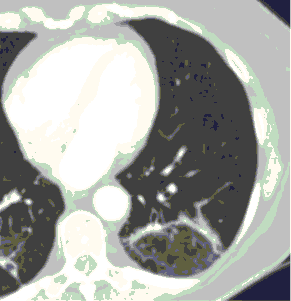

6. Внутривенное контрастирование при КТ у пациентов с известной/предполагаемой вирусной (COVID-19) пневмонией проводится при подозрении на заболевания и патологические состояния, диагностика которых невозможна без использования контрастных средств (ТЭЛА, онкологические заболевания др.). Внезапный рост концентрации Д-димера в анализах крови и клиническое подозрение на ТЭЛА являются важными критериями для выполнения КТ-ангиопульмонографии при условии, что ее положительный результат может оказать влияние на лечение и ведение пациента.

7. Решение о внутривенном контрастировании принимает врач-рентгенолог совместно с врачом, направляющим пациента на КТ. Введение контрастного средства выполняется в соответствии с общими правилами проведения рентгеноконтрастных исследований.